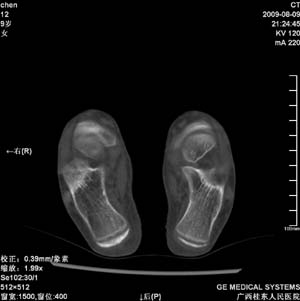

标题: PED2867:右侧内踝肿胀,骨质改变,请各位老师会诊 [打印本页]

标题: PED2867:右侧内踝肿胀,骨质改变,请各位老师会诊

九岁小朋友,近期左侧内踝疼痛,局部肿胀,平时无特殊,近期经常溜干冰

对不起,是右侧内踝肿胀

双踝关节骨质及发育未见异常。

左侧内踝密度增高,请结合临床!